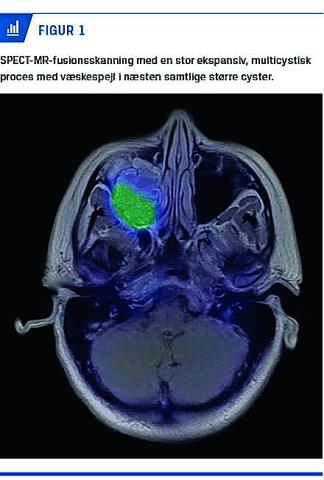

En CT viste en stor, delvist forkalket tumor, der havde cystiske komponenter og forskød maxilvæggene, men der var ingen ossøs gennemvækst. På en MR-skanning fandt man en stor ekspansiv, multicystisk proces med væskespejl i næsten samtlige større cyster (Figur 1). En histologisk undersøgelse gav den endelige diagnose: aneurismal knoglecyste.